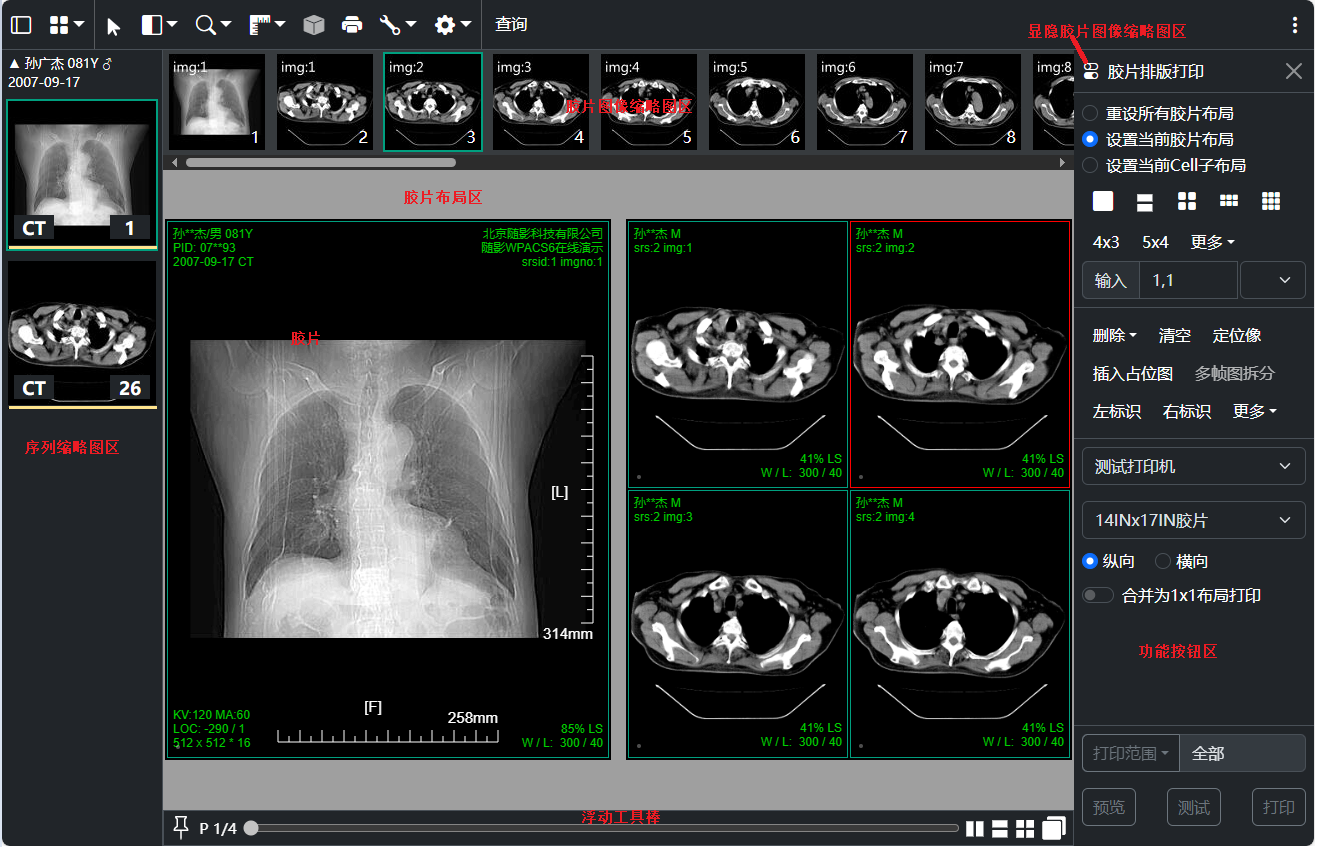

三、胶片打印和排版

胶片功能按钮区的按钮、菜单以及打印机列表和胶片列表用户可自定义修改配置;

拖到序列缩略图到胶片排版窗口可追加当前序列图像到胶片; 拖到胶片图像缩略图上可在当前图像之前或之后插入此序列所有图像;

胶片图像缩略图区域的图像会顺序布局到胶片上;可以针对每个胶片做不同的排版布局同时支持嵌套布局

拖动胶片图像缩略图到其它胶片缩略图上可在其之前 / 之后插入拖动图像(拖动时按下ctrl则复制拖动图像然后插入) 或者 和 拖动图像交换位置;

拖动胶片图像缩略图到胶片的cell格则在此cell格显示此图像,相当于和当前cell格上的图像交换位置

拖动胶片图像缩略图到胶片布局区则从胶片排版窗口删除此图像; 还支持删除胶片图像,清空图像删除指定序号图像等等

支持保存布局模板: 用户可在自定义按钮事件中保存当前胶片布局信息;后续可加载保存的布局模板

支持胶片重打或重现: 用户可在自定义按钮事件中保存当前胶片任务信息;后续可加载重现当前排版布局以及显示效果